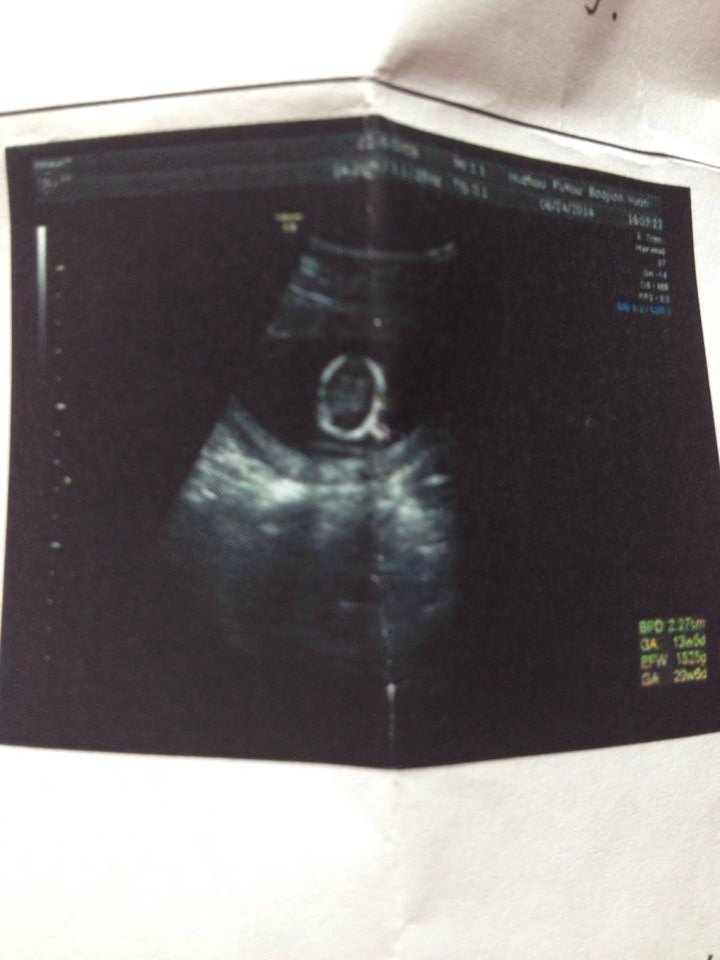

请问能看出是单双胞胎么? 请问能看出是单双胞胎么? 点击展开 love520 2014-07-10 14:39 为您推荐: 其他回答 你好,一般这个时候像你这样的情况应该是单胎的吧!因为这个时候只有一个孕囊!而且你可以让你的医生看 adfaffq 2014-07-10 16:10 相关问题 请问能看出是双胞胎还是单胞胎吗? 双胞胎不能做唐筛么? 单胎和双胞胎预产期一样么?还是会提前